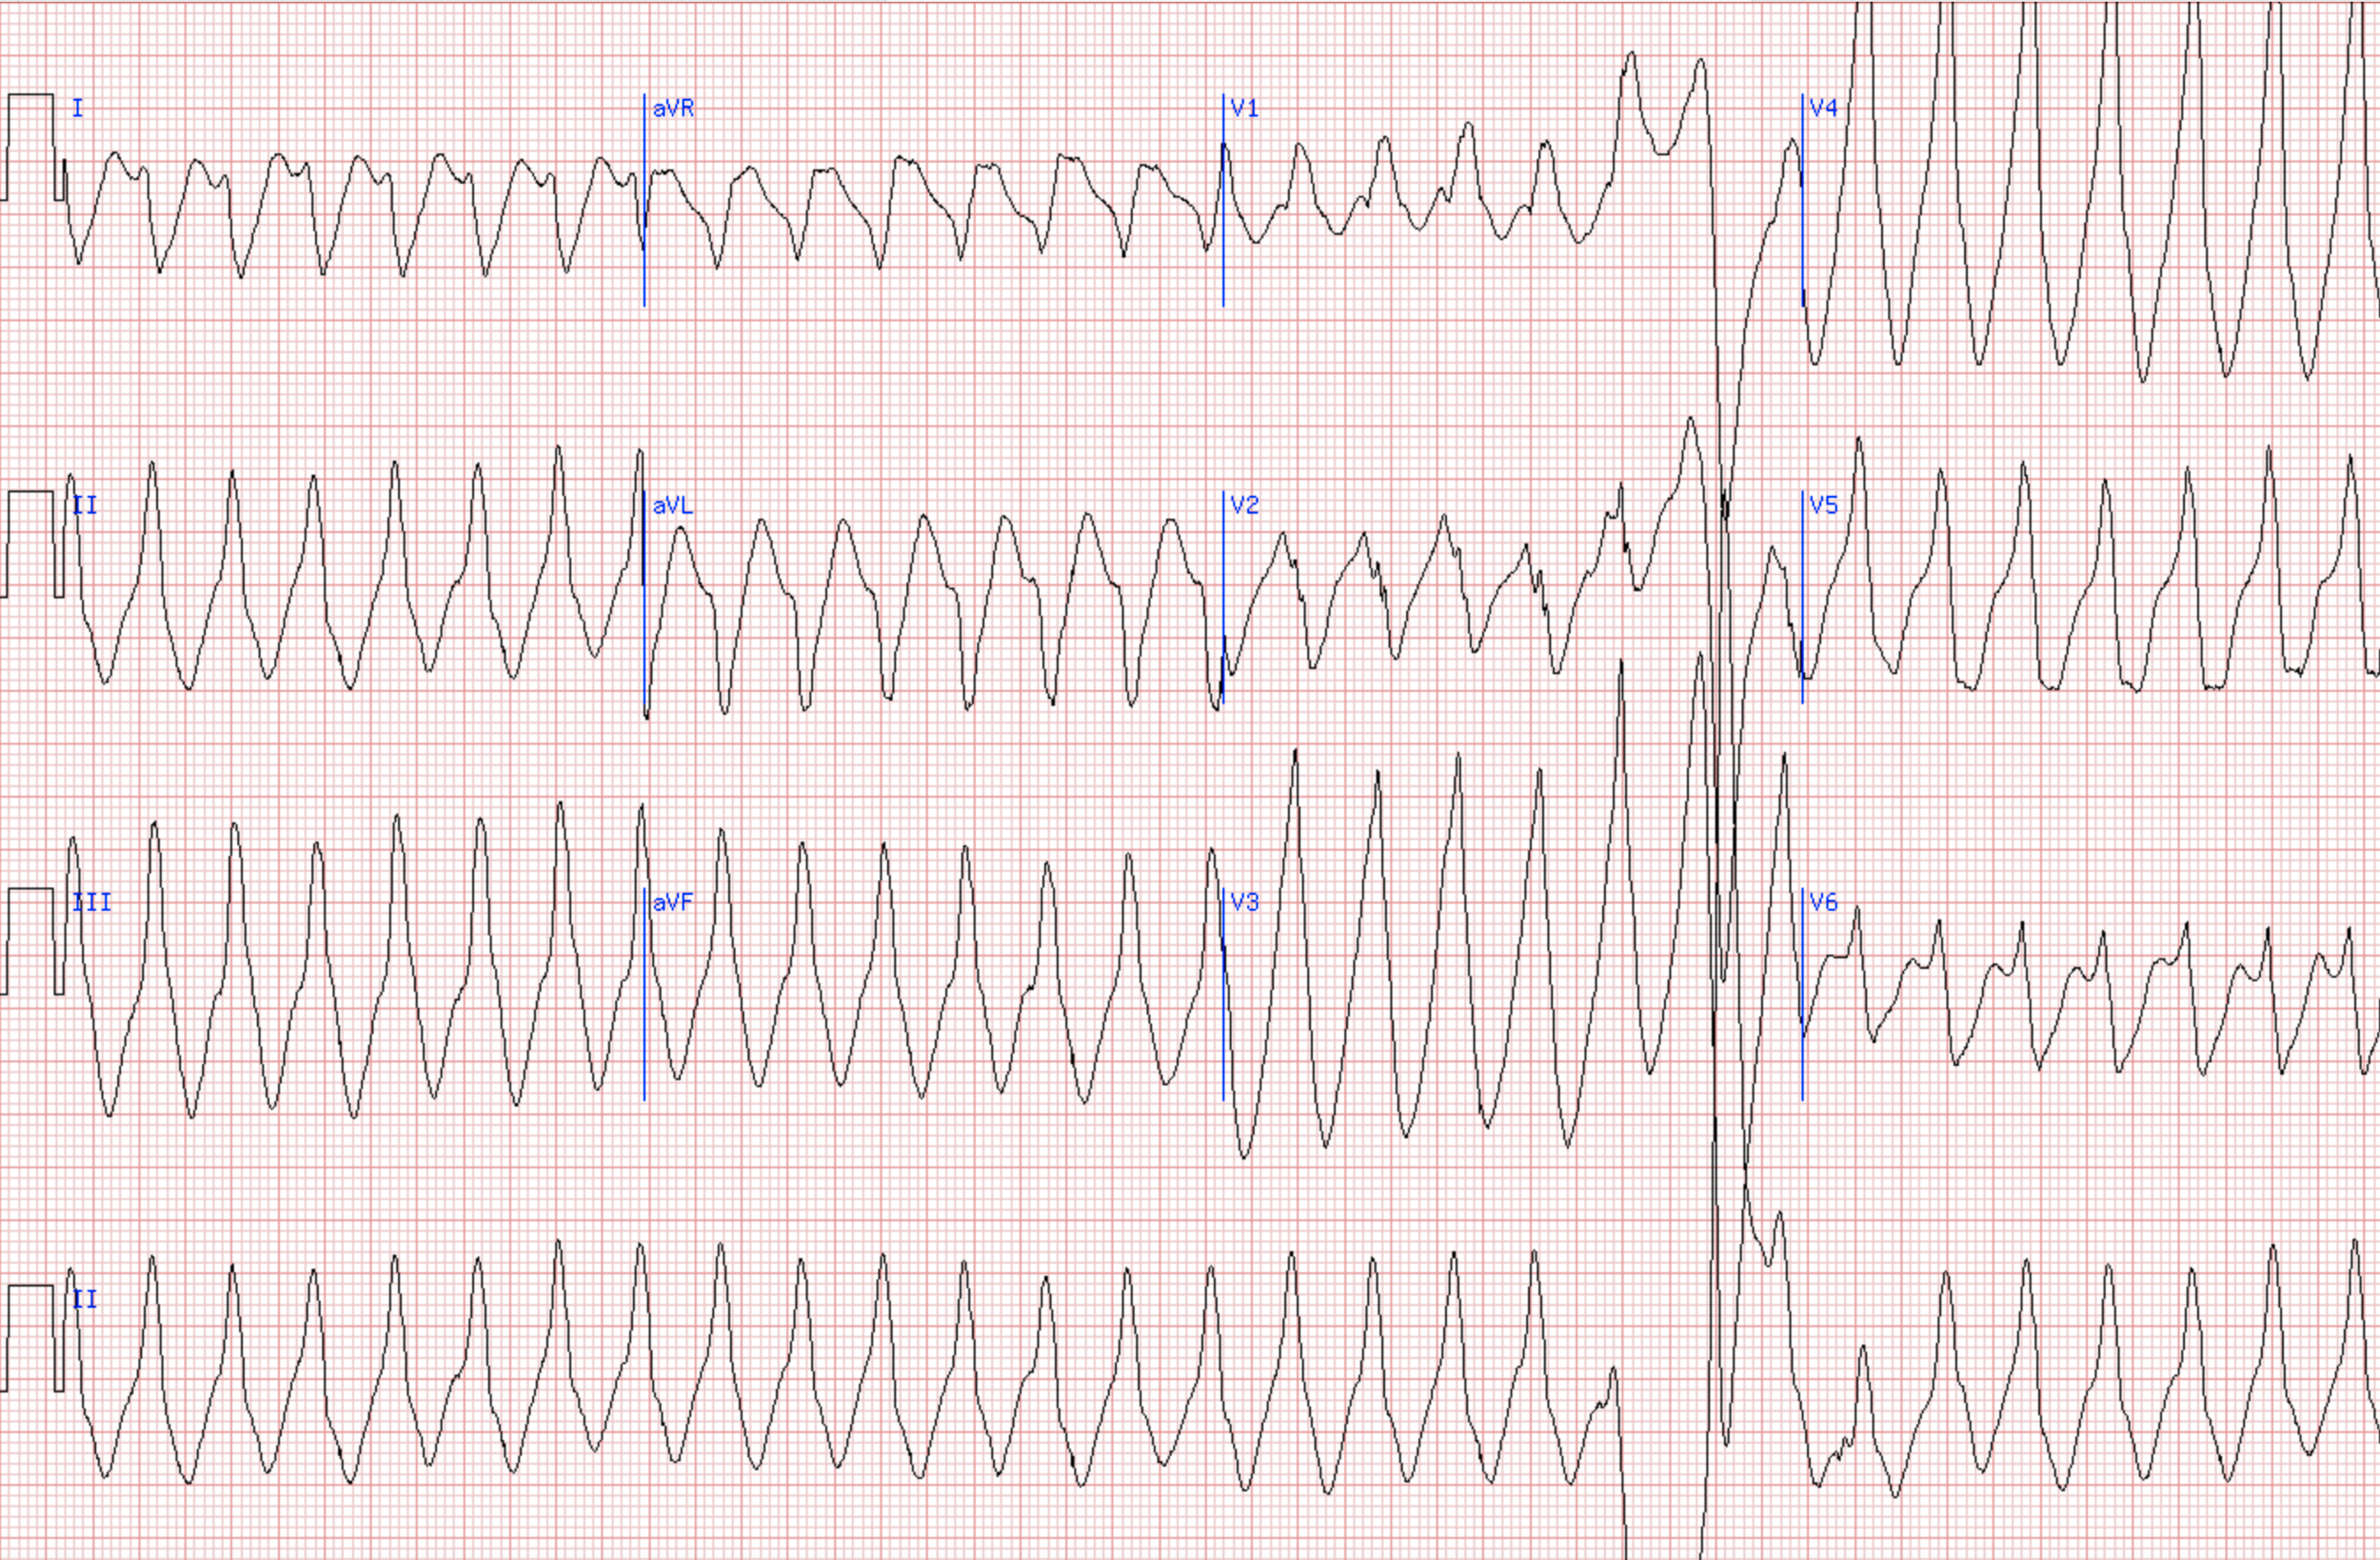

“The Staff of Professors of the Royal Caroline Institute has on 23rd October, 1924, decided to confer this year’s Nobel Prize in Physiology or Medicine to the Professor of Physiology at the University of Leiden, Willem Einthoven, for his discovery of the mechanism of the electrocardiogram.

“Einthoven’s name is linked partly with the design of a physical instrument, the string galvanometer, partly with the so-called electrocardiogram, a record of the electrical potential fluctuations at the surface of the body, which accompany the heart beat. The heart beat, like the piston movement of a steam engine, is a cyclic process. Behind this process lies, in the first place, a similarly cyclic process in the heart muscle.

…

“The same mechanism governing the characteristics of the electrocardiogram, also governs the characteristics of the mechanical process during the heart beat. We should remember in this connection that the mechanical process not only consists of the succession of the stimulation of the separate parts of the heart compartments, but also of the cooperation of the individual parts of the heart wall which form the essential condition for the mechanical effect in the individual ventricle or in the individual auricle. A deficiency in this cooperation can, with regard to the mechanical effect, be as fatal as a valvular insufficiency. Today, the importance of the mechanism discovered by Einthoven can easily be realized.”